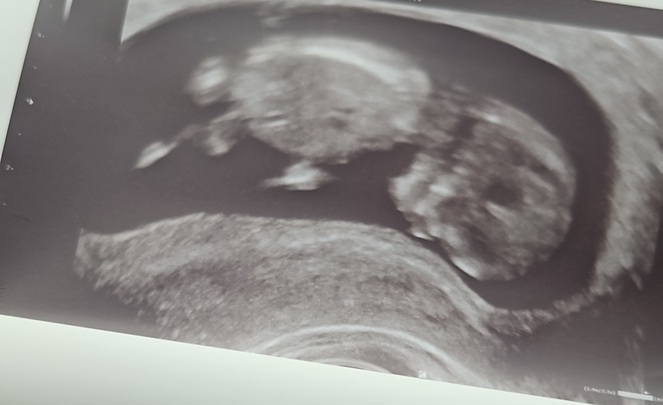

Alles kommt anders als gedacht... - Tagebücher aus der Schwangerschaft von Marie aus bei Heidelberg